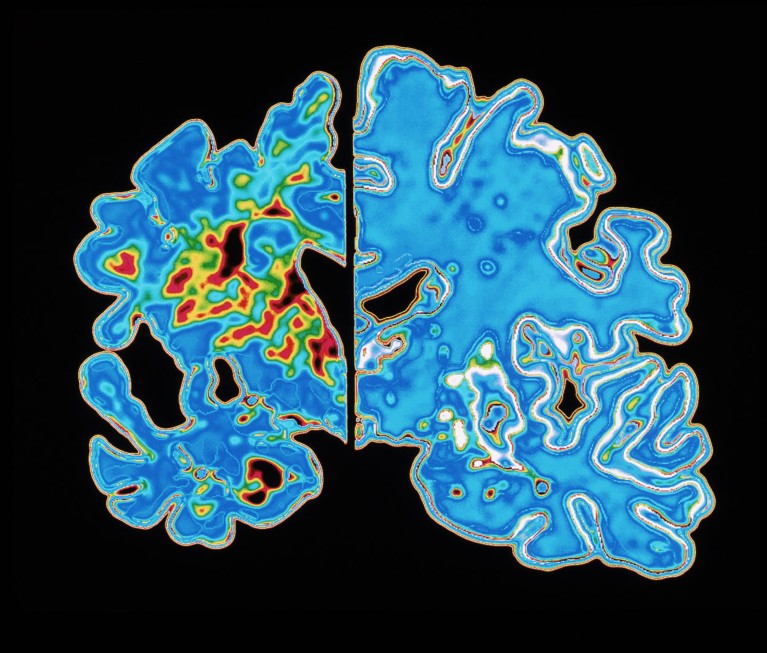

Abnormal tau proteins can form tangled fibres that accumulate in the brains of people with Alzheimer’s (slice at left). (Brain without Alzheimer’s shown at right.)Credit: Alfred Pasieka/Science Photo Library

Abnormal tau proteins can form tangled fibres that disrupt communication among the brain’s nerve cells. Brain-imaging tests that detect tangled tau are sometimes used when diagnosing Alzheimer’s, and preliminary studies suggest that such tests might also be able to predict when a person’s Alzheimer’s symptoms will appear2,3.